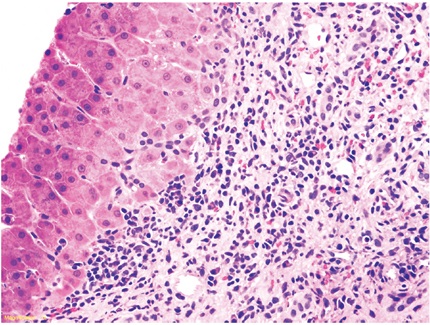

- Inflamación portal: cualquier grado de inflamación portal con presencia de una población heterogénea de células inflamatorias, tales como linfocitos T activados, inmunoblastos y eosinófilos, acompañados de algunos plasmocitos y polimorfonucleares neutrófilos. Puede existir leve o mínima inflamación lobulillar, en parches (Figura 5)

- Lesión inflamatoria de la vía biliar: ductulitis o presencia de células inflamatorias linfoides en el epitelio de ductos pequeños (<30 µm) y cambios degenerativos dados por aumento de la relación núcleo/citoplasma, hipercromasia y pleomorfismo nuclear, seudoestratificación nuclear o alteración de la polaridad, mitosis, vacuolización paranuclear del epitelio ductal; puede existir ruptura de la membrana basal (Figura 6).